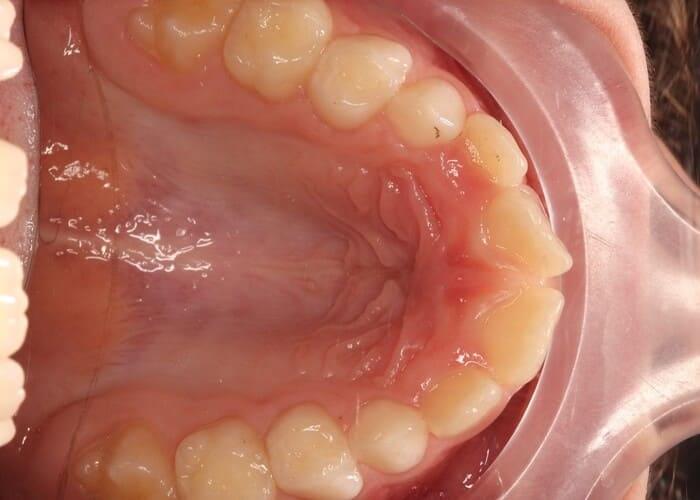

Хлопичк 8 років

Провели розширення верхньої щелепи за допомогою апарату Марко-Роса,вирівнюємо зубний ряд за допомогою часткової брекет системи